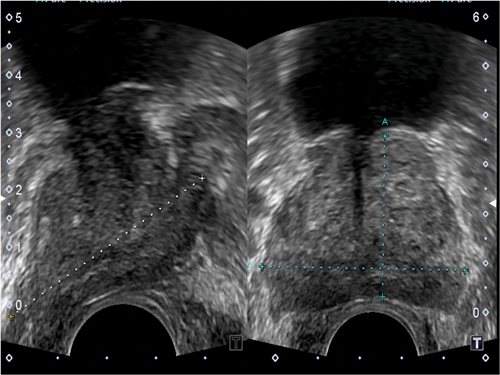

Figure 2: Ultrasound axial and longitudinal image with the gland size being measured.